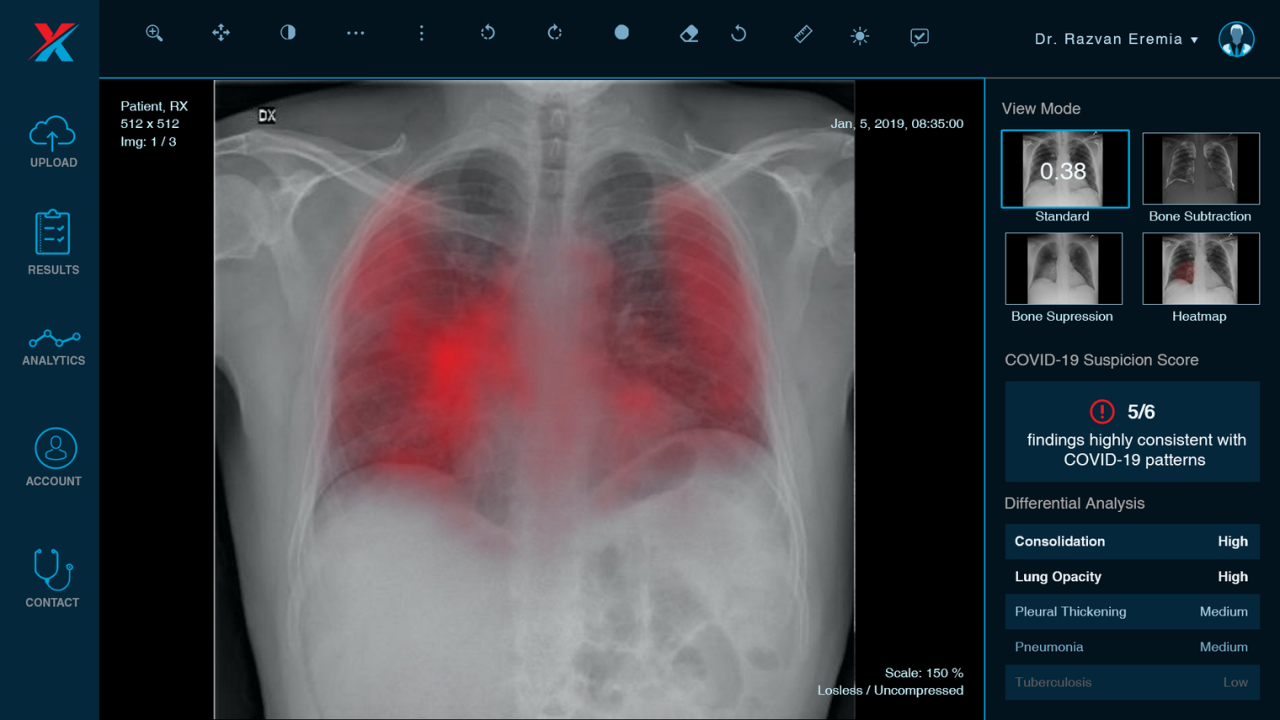

La baza sistemului de triaj stă un scor de evaluare dezvoltat de echipa de radiologi a XVision, raportat la scoruri și standarde folosite în momentul de față la nivel global. Acesta descrie cât de similare consideră algoritmul că sunt pattern-urile radiologice din radiografia pacientului cu cele întâlnite în cazurile de COVID-19

Ca parte a triajului, după ce radiografia este efectuată în laboratorul mobil, aplicația XVision furnizează un rezultat foarte rapid care este analizat de doctori, alături de radiografia inițială. În funcție de acesta se ia o decizie privind cazul medical respectiv. XVision detectează semne de pneumonie, chiar și incipientă, și atribuie un grad de asemănare a pattern-ului radiologic de pneumonie cu cea specifică în COVID-19.